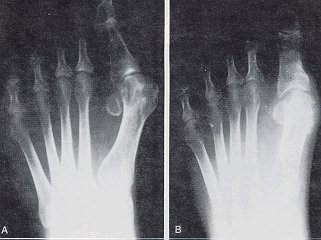

Deformities of severe hallux abducto valgus contain a hallux abductus angle of 40° or greater. The first intermetatarsal angle is 15° or greater, and generally in severe HAV, the joint position is usually subluxed (Fig. 3).

Figure 3

An example of a severe HAV deformity.

1. The preoperative radiograph.

2. The same patient 5 years after surgery.